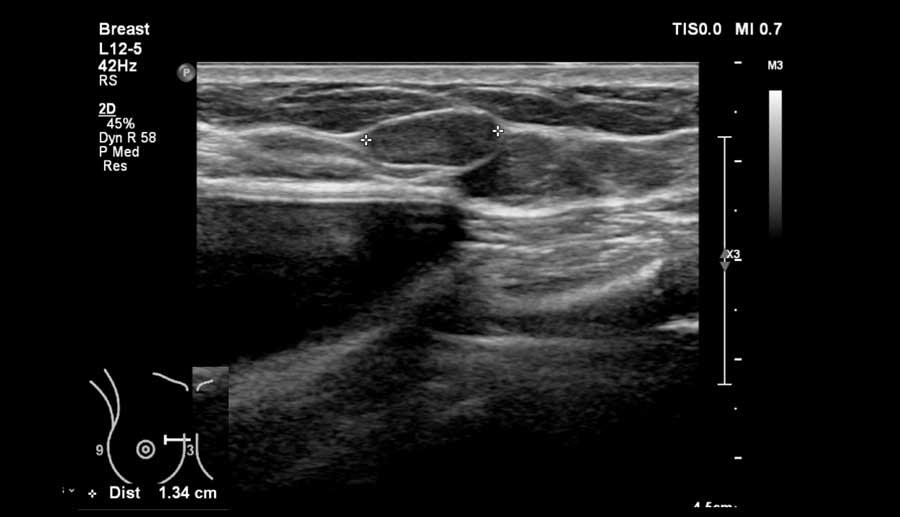

Hình ảnh cho thấy một tổn thương mà thoạt nhìn có vẻ giống u xơ tuyến vú.

Tuy nhiên, có hai điểm không phù hợp.

Thứ nhất, tuổi của bệnh nhân là 49 tuổi và thứ hai, bờ phía sau của tổn thương có một số chỗ không đều.

Sinh thiết đã được thực hiện và khối này được xác định là ung thư.